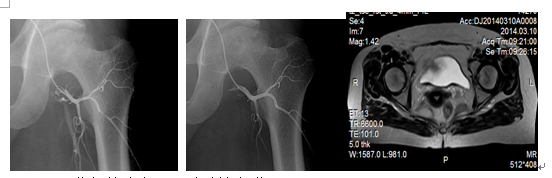

股骨头坏死又称股骨头缺血性坏死,病因复杂,是因各种原因导致股骨头供血不足,营养缺乏而致骨质破坏,治疗困难,最终导致关节畸形!微创介入治疗通过局部溶栓和扩张血管结合中药治疗以改善股骨头血供,从而解决股骨头营养,促进股骨头修复,对0--II期病变效果尤为显著,对III-IV期病变也有很好的止痛效果,结合活血化淤中药治疗,疗效独特!

典型病例:女、63岁,2010年10月在我院MR检查发现双侧股骨头缺血性坏死II期,行三次介入术后。2014年复查提示病变基本愈合。